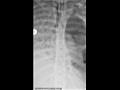

نشرت صحيفة "ديلي ميل" البريطانية صورًا صادمة لرئة لفتاة إسبانية تعافت من فيروس كورونا، إذ أُجري لها عملية جراحيه دقيقة لاستبدالهما كي تتمكن من العيش بطريقة طبيعية.

وذكرت الصحيفة أن بعض الحالات المتعافية من كورونا تحتاج إلى عملية زرع رئة؛ لأن الفيروس يهاجمها بطريقة عنيفة ويحدث بها ثقوب تعيق من عملية التنفس.

وأجرى الجراحون للفتاة العشرينية عملية زرع الرئة بشيكاغو بعد تعافيها من فيروس كورونا، بعد أن ظلت على جهاز التنفس الصناعي وجهاز القلب والرئة لمدة شهرين قبل الجراحة.

وقال الدكتور أنكيت بهارات استشاري أمراض الرئة والرعاية الحرجة، إن اجراء العملية استمر لمدة 10 ساعات لأن الفيروس ترك رئتيها مملوءتين بالثقوب وكاد يقترب من جدار القفص الصدري، وأن هذه العملية هي فرصتها الوحيدة في البقاء.